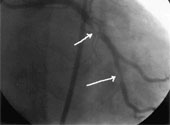

PCI reprezintă o procedură utilizată pentru a trata sindromurile coronariene acute. PCI implică deschiderea unui vas de sânge blocat prin introducerea şi umflarea unui balon cu tub în vârf. Uneori este montat un stent pentru a menţine permeabil vasul de sânge.

Cercetătorii au clasificat evenimentele BCV/IM în trei categorii: tromboză de stent (atunci când un cheag de sânge s-a format în interiorul stentului), legate de procedură (în cadrul PCI sau intervenţiilor chirurgicale de by-pass) sau spontane (nu sunt legate nici de stenturi, nici de procedură, dar indicând o tromboză a unei artere, diferită de cea care a cauzat primul sindrom coronarian acut).